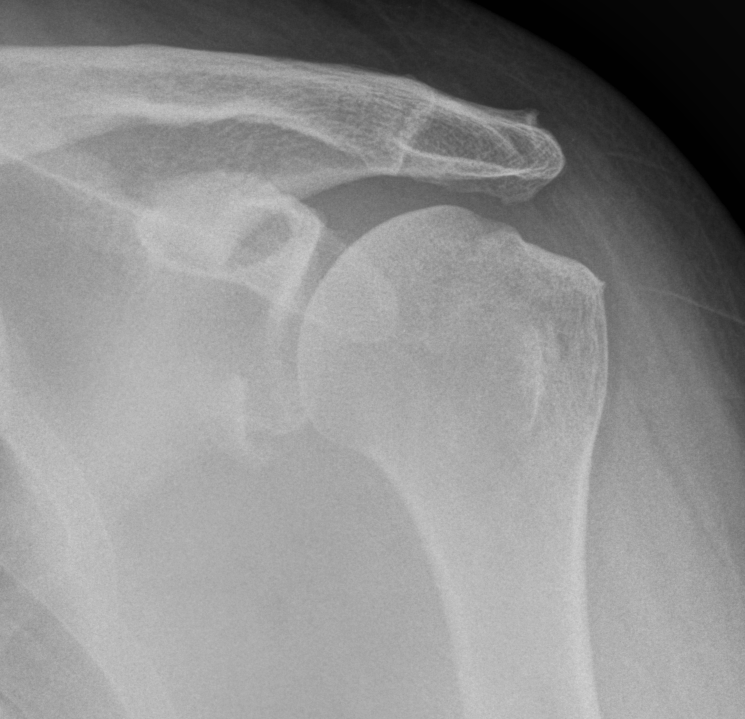

Bankart fracture of glenoid rim